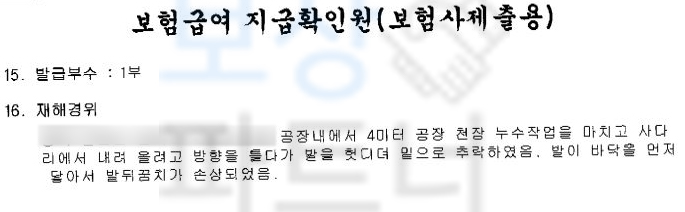

청주시 거주하시는 김@@님은 공장의 천장 누수 작업을 마치고 사다리에서 내려 가기 위해 방향을 틀던 중 발을 헛디뎌 4미터 높이에서 추락하였으며 발이 바닥에 먼저 닿아 발뒤꿈치 골절 즉 종골골절 진단을 받았습니다.

위 실제 작성하신 사례처럼 사고 경위를 그.대.로 적으시고 사고 발생시 바로 산재 신청을 진행하시는 것이 좋습니다. 산재 신청은 개인적으로 혹은 병원 원무과의 도움을 받아 큰 어려움없이 신청하실 수 있습니다.